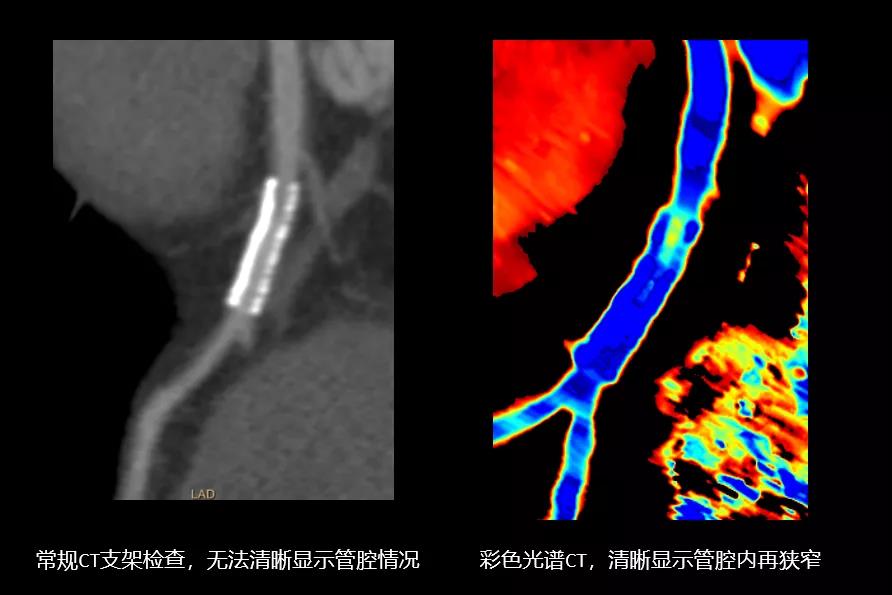

简单来说,普通的CT显示的图像是黑白的,只能提供单一参数诊断。而彩色光谱CT,可将一次采集的图像在不同能量级下彩色显示,能发现普通CT不能发现的病灶,并准确分析病灶的结构、大小、血供和代谢等,有助于发现隐匿病灶,帮助医生做出更加精准、“超前”的诊断结果。

该设备实现了心脏一体化诊疗。传统通常是使用CT做心脏冠脉的检查,用核磁或核医学做心脏心肌的检查。但IQon光谱CT首开先河,实现冠脉加心肌一站式解决,不仅判断冠脉形态病变,还能精确诊断心肌缺血、心肌纤维化甚至心肌炎病变,实现了一站式全息心脏成像,方便快捷,避免了重复检查。